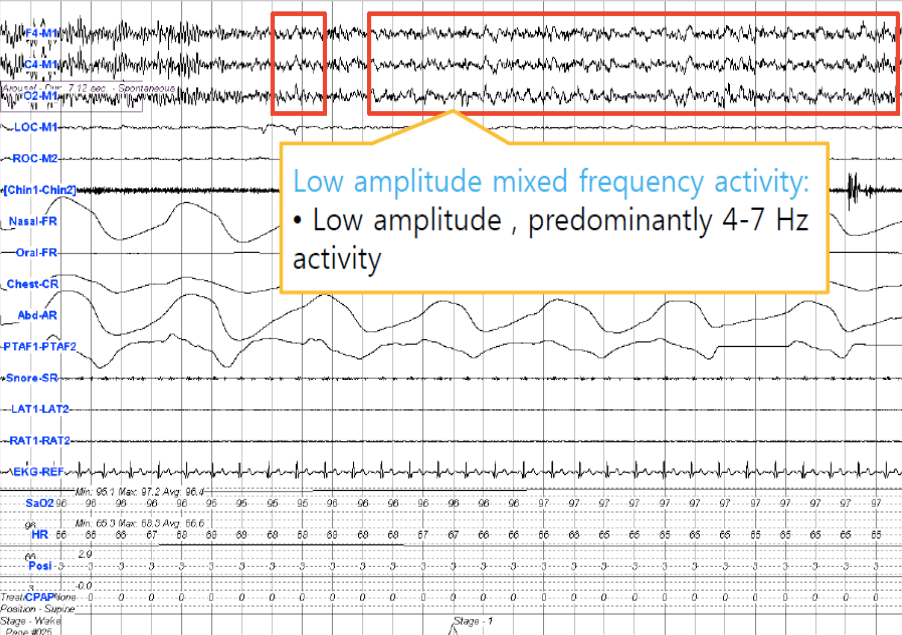

N1 Sleep (psg criteria)

• Less than 50% Alpha

• If no alpha than any of the following:

1) 4 to 7 Hz background with slowing greater than 1 Hz from stage wake

3) slow rolling Eye movements

• LAMF EEG (resembles N1)(Alpha activity may appear)